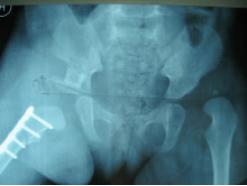

右髋切开复位、Pemberton骨盆截骨 股骨近端短缩去旋转截骨术后

右侧术后8个月